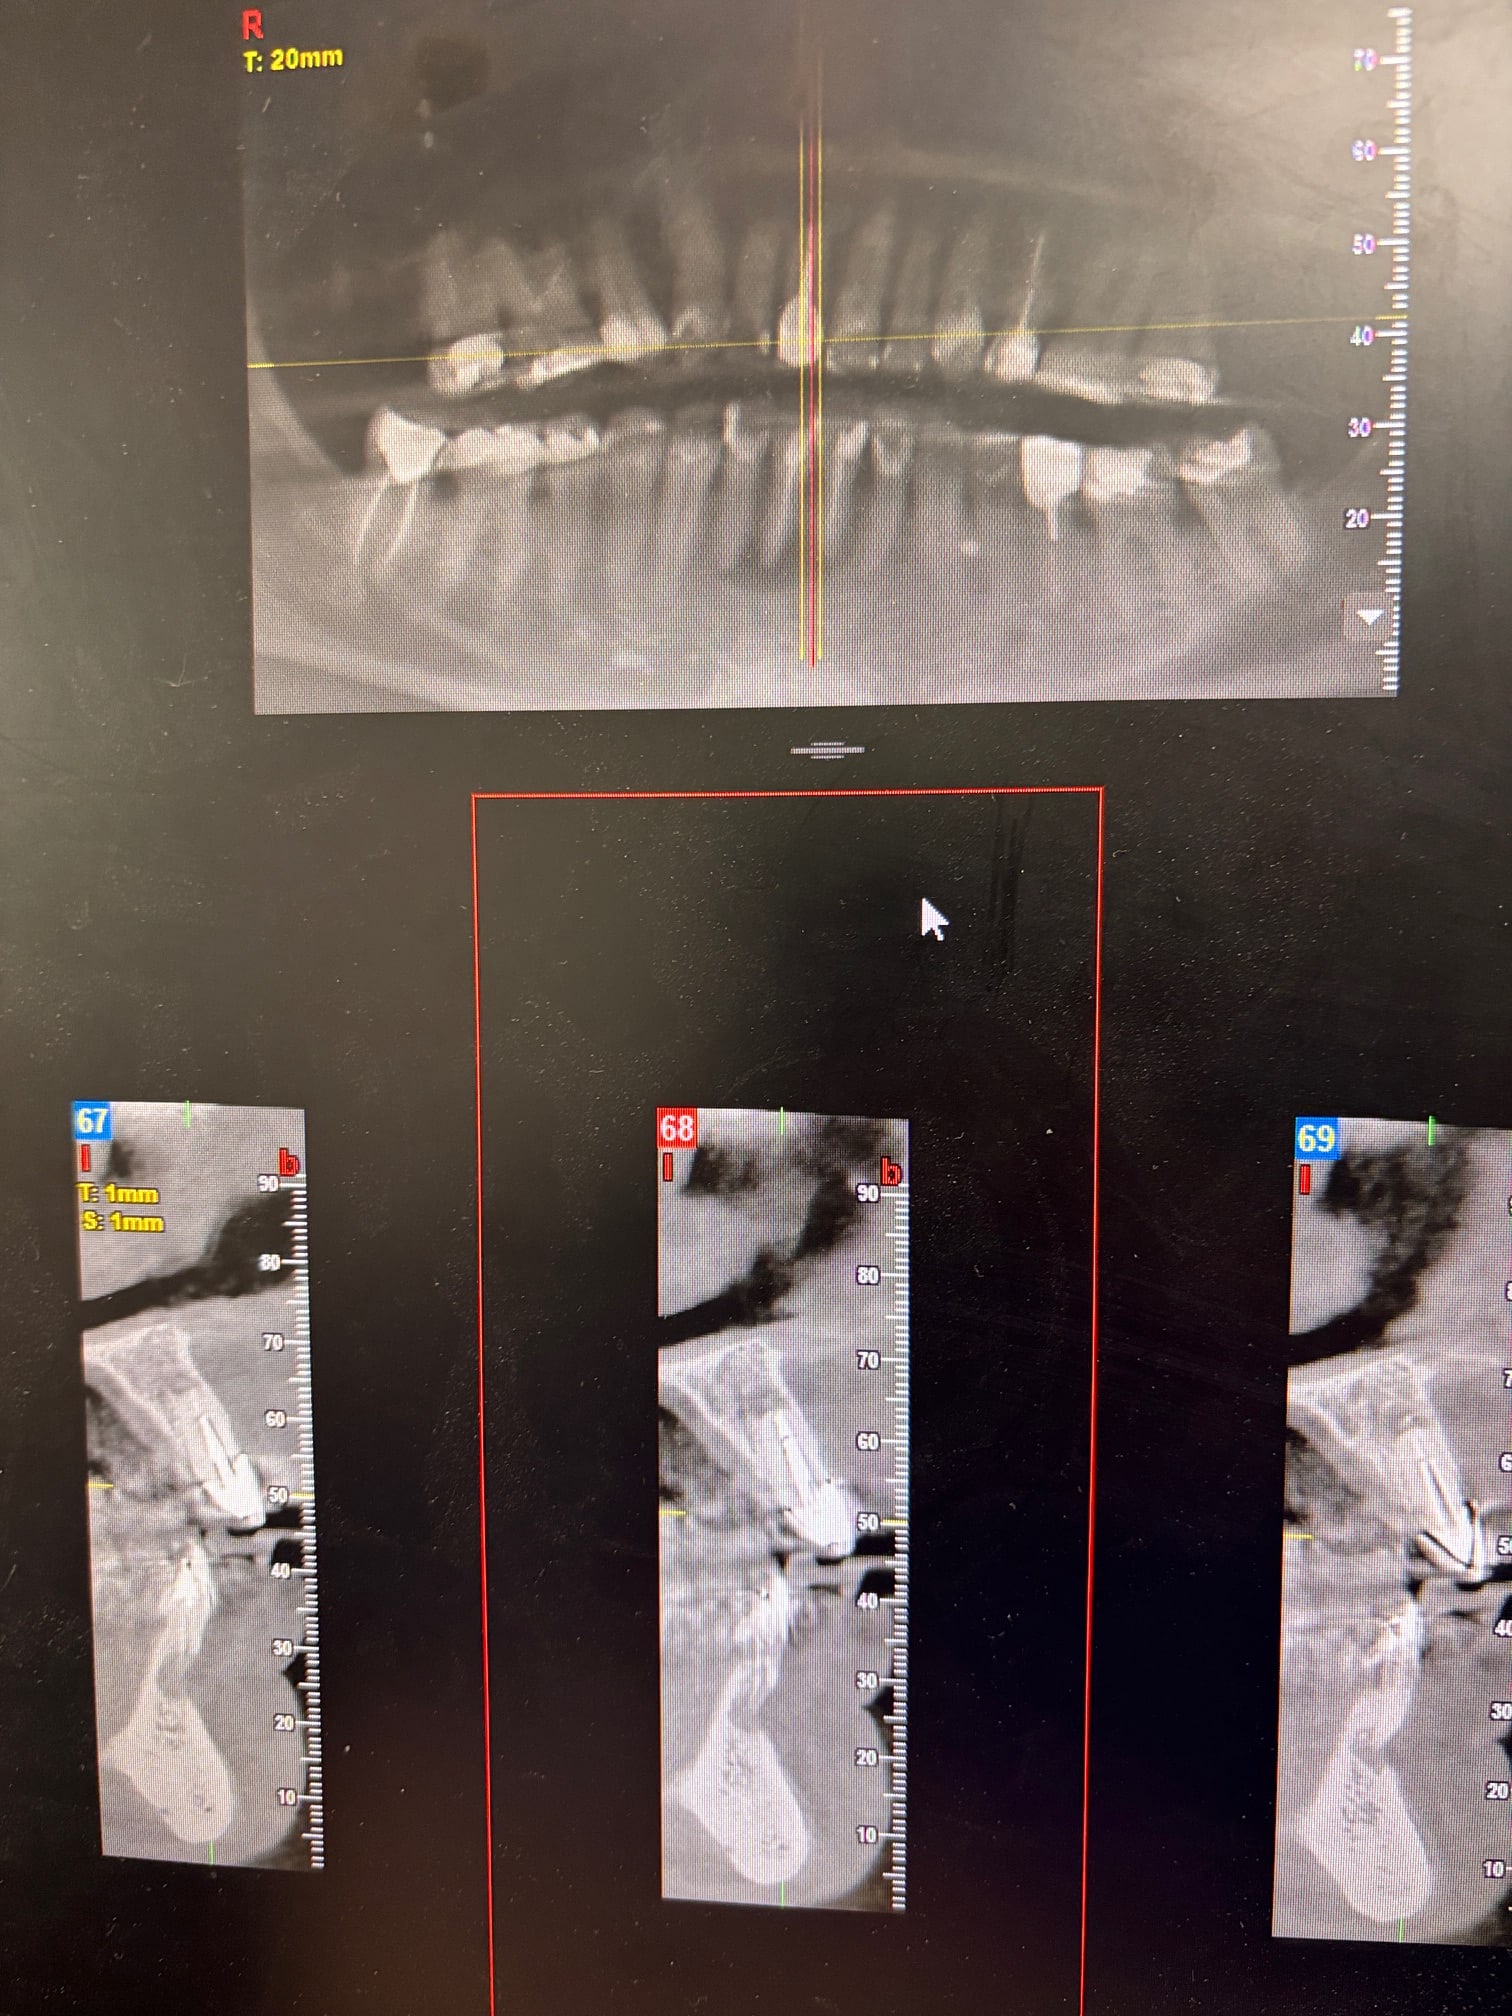

En revanche, rien à voir, mais pourquoi un cbct grand champ avant consentement aux soins pour un des sextants visibles sur une rétro ; là par exemple, sextant 7, quand tu vois à l examen clinique des dents qui ont cette gueule, t'es quasi sûr de voir des LIPOE sur la rétro, perso je fais déjà une proposition de traitement pour ça, puis si le patient accepte on regarde le reste.

Parce que si ton patient refuse ta pdt, il aura été irradié pour rien.

Ben je fais juste mon taf sans me poser de question. Ca a commencé par des rétros avec des images moyennasses . Puis de fil en aiguille, le patient me décrit des épisodes de sinusites assez fréquents.

Vu qu’il y avait des images aux 4 coins, le CB permet de tout vérifier. Et si mon patient ne fait rien, c’est pas mon soucis. Il part avec son cone beam et moi je rentre chez moi en ayant la sensation d’avoir fait mon job. À savoir: examen clinique et radio, entretien avec le patient puis présentation du diag et du plan de traitement. La suite est entre ses mains, pas entre les miennes.